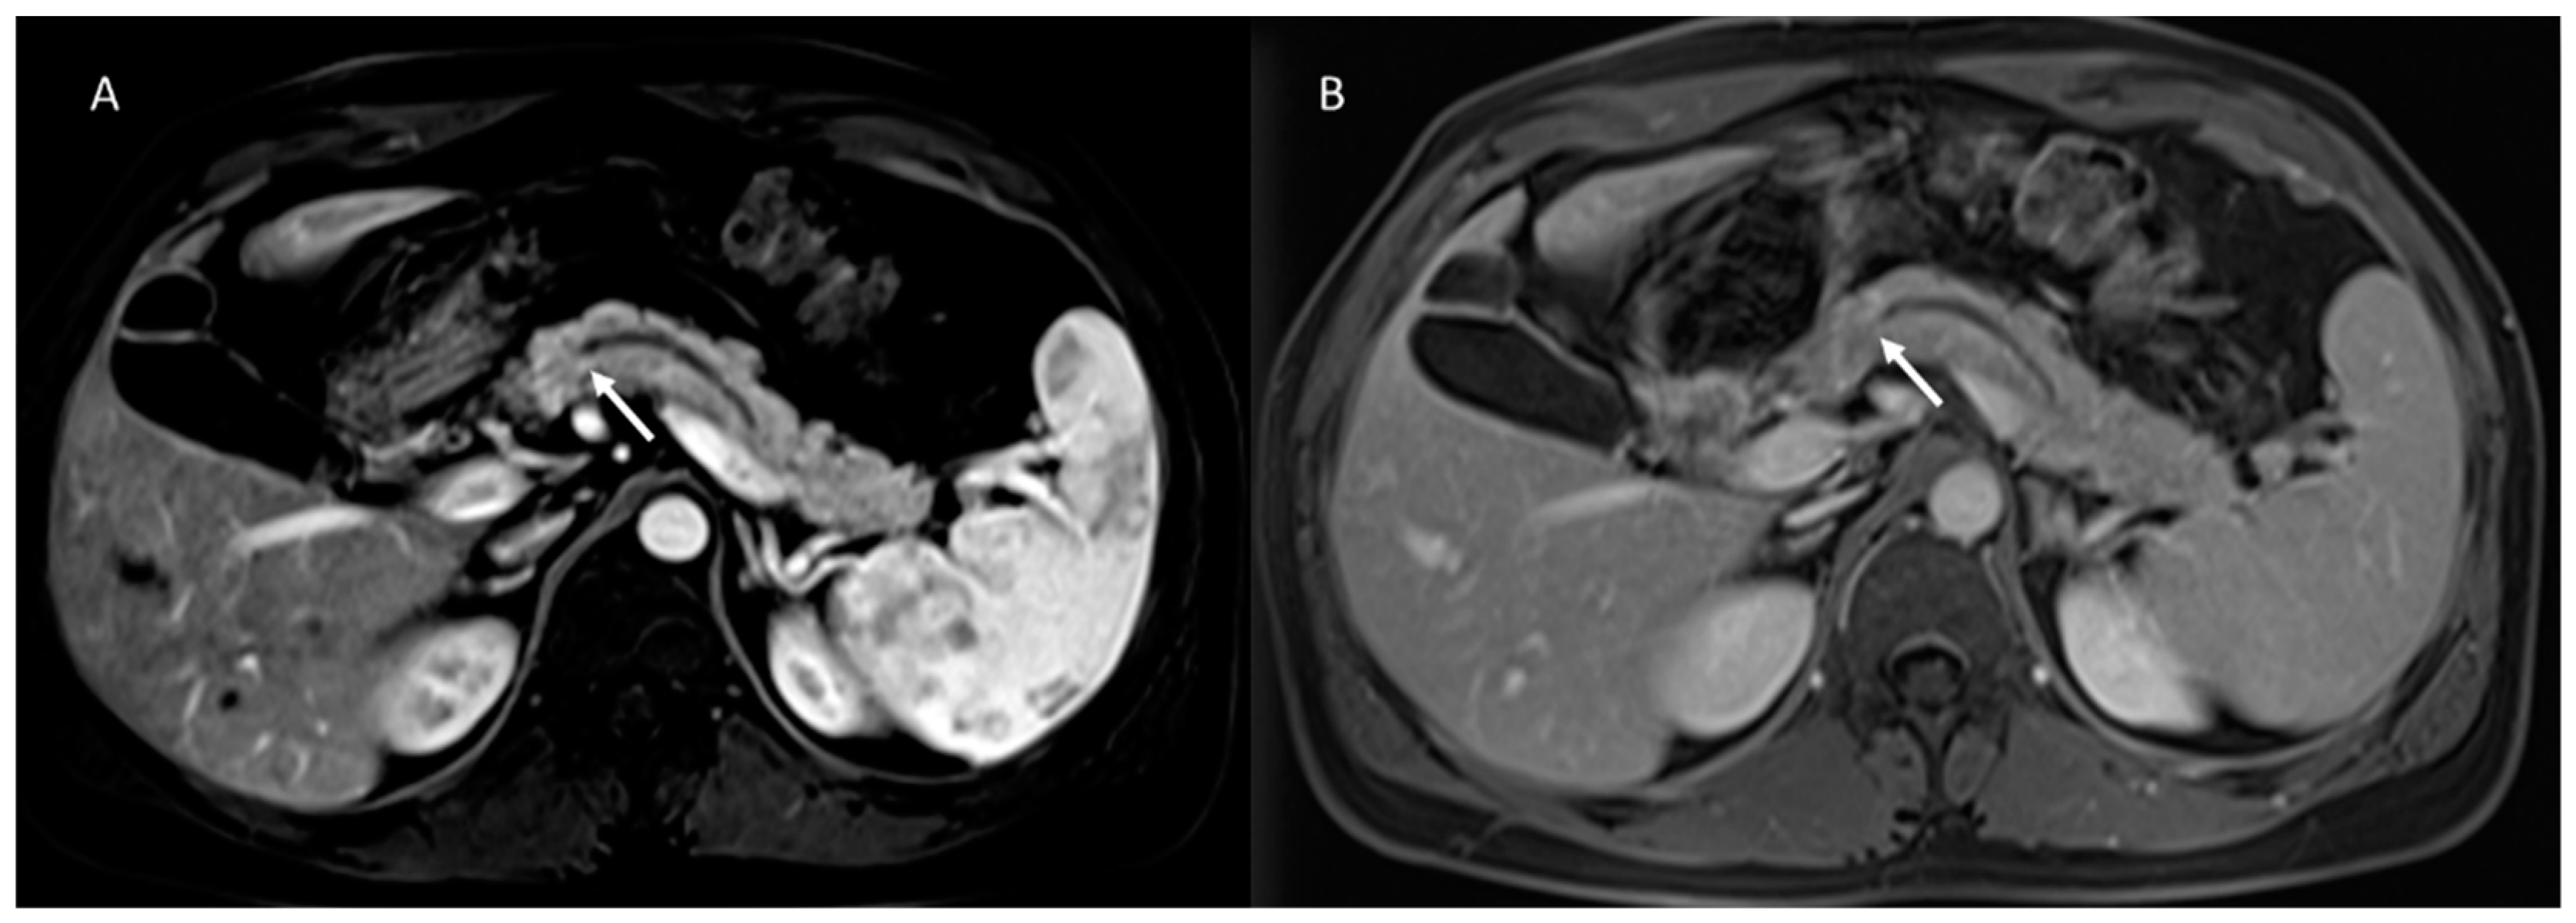

- Yoon, J.G.; Smith, D.; Ojili, V.; Paspulati, R.M.; Ramaiya, N.H.; Tirumani, S.H. Pancreatic cystic neoplasms: A review of current recommendations for surveillance and management. Abdom. Radiol. 2021, 46, 3946–3962. [Google Scholar] [CrossRef]

- Lee, H.-J.; Kim, M.-J.; Choi, J.-Y.; Hong, H.-S.; Kim, K. Relative accuracy of CT and MRI in the differentiation of benign from malignant pancreatic cystic lesions. Clin. Radiol. 2011, 66, 315–321. [Google Scholar] [CrossRef] [PubMed]

- Sainani, N.I.; Saokar, A.; Deshpande, V.; Castillo, C.F.-D.; Hahn, P.; Sahani, D.V. Comparative Performance of MDCT and MRI With MR Cholangiopancreatography in Characterizing Small Pancreatic Cysts. Am. J. Roentgenol. 2009, 193, 722–731. [Google Scholar] [CrossRef]

- Sahani, D.V.; Kambadakone, A.; Macari, M.; Takahashi, N.; Chari, S.; Castillo, C.F.-D. Diagnosis and Management of Cystic Pancreatic Lesions. Am. J. Roentgenol. 2013, 200, 343–354. [Google Scholar] [CrossRef] [PubMed]

- Kim, T.S.; Castillo, C.F.-D. Diagnosis and Management of Pancreatic Cystic Neoplasms. Hematol. Clin. N. Am. 2015, 29, 655–674. [Google Scholar] [CrossRef]